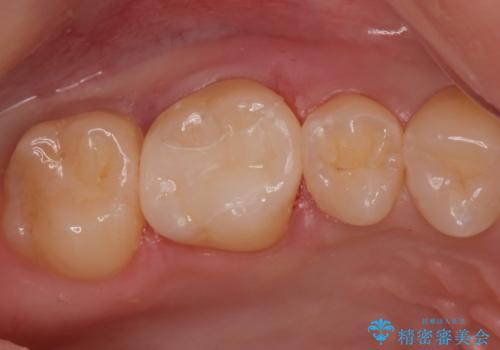

コンタクトカリエスの治療。(e-maxインレー)

- 歯が染みるとの事で来院。歯と歯の間にカリエス(虫歯)が出来ていて穴が空いていました。

拡大鏡下で虫歯を全て取り除き、e-maxインレーで治療を行いました。

適合の良い詰め物が入りました。